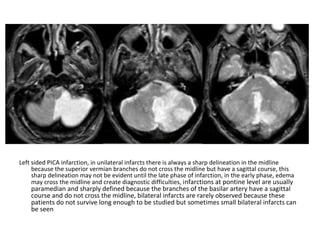

Left sided PICA infarction, in unilateral infarcts there is always a sharp delineation in the midline

because the superior vermian branches do not cross the midline but have a sagittal course, this

sharp delineation may not be evident until the late phase of infarction, in the early phase, edema

may cross the midline and create diagnostic difficulties, infarctions at pontine level are usually

paramedian and sharply defined because the branches of the basilar artery have a sagittal

course and do not cross the midline, bilateral infarcts are rarely observed because these

patients do not survive long enough to be studied but sometimes small bilateral infarcts can

be seen